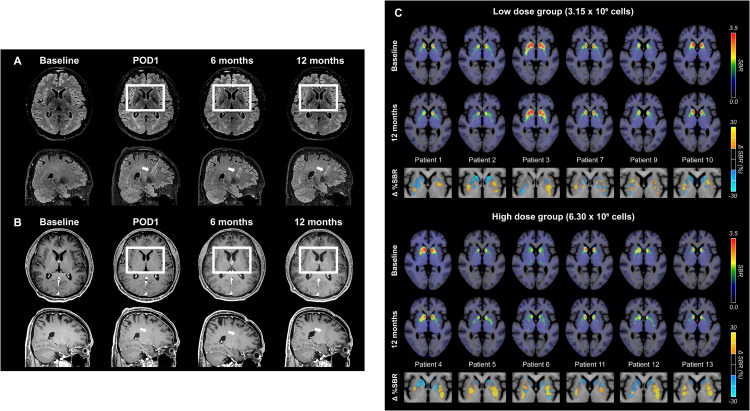

术后MRI显示,移植区域未出现肿瘤或明显炎症反应,细胞被准确植入壳核目标区域,初步证明手术和细胞定位的安全性与可控性。

更关键的证据来自多巴胺转运体PET成像。与基线相比,后背侧壳核区域的DAT信号在高剂量组明显升高,且这种变化与患者停药状态下的运动改善程度呈显著相关。这意味着,影像学上观察到的多巴胺能功能增强,与临床症状的改善方向一致。(图6)

这些结果共同表明:移植的多巴胺祖细胞不仅在脑内存活,而且在关键运动环路中实现了功能性整合,并与实际运动改善相对应。